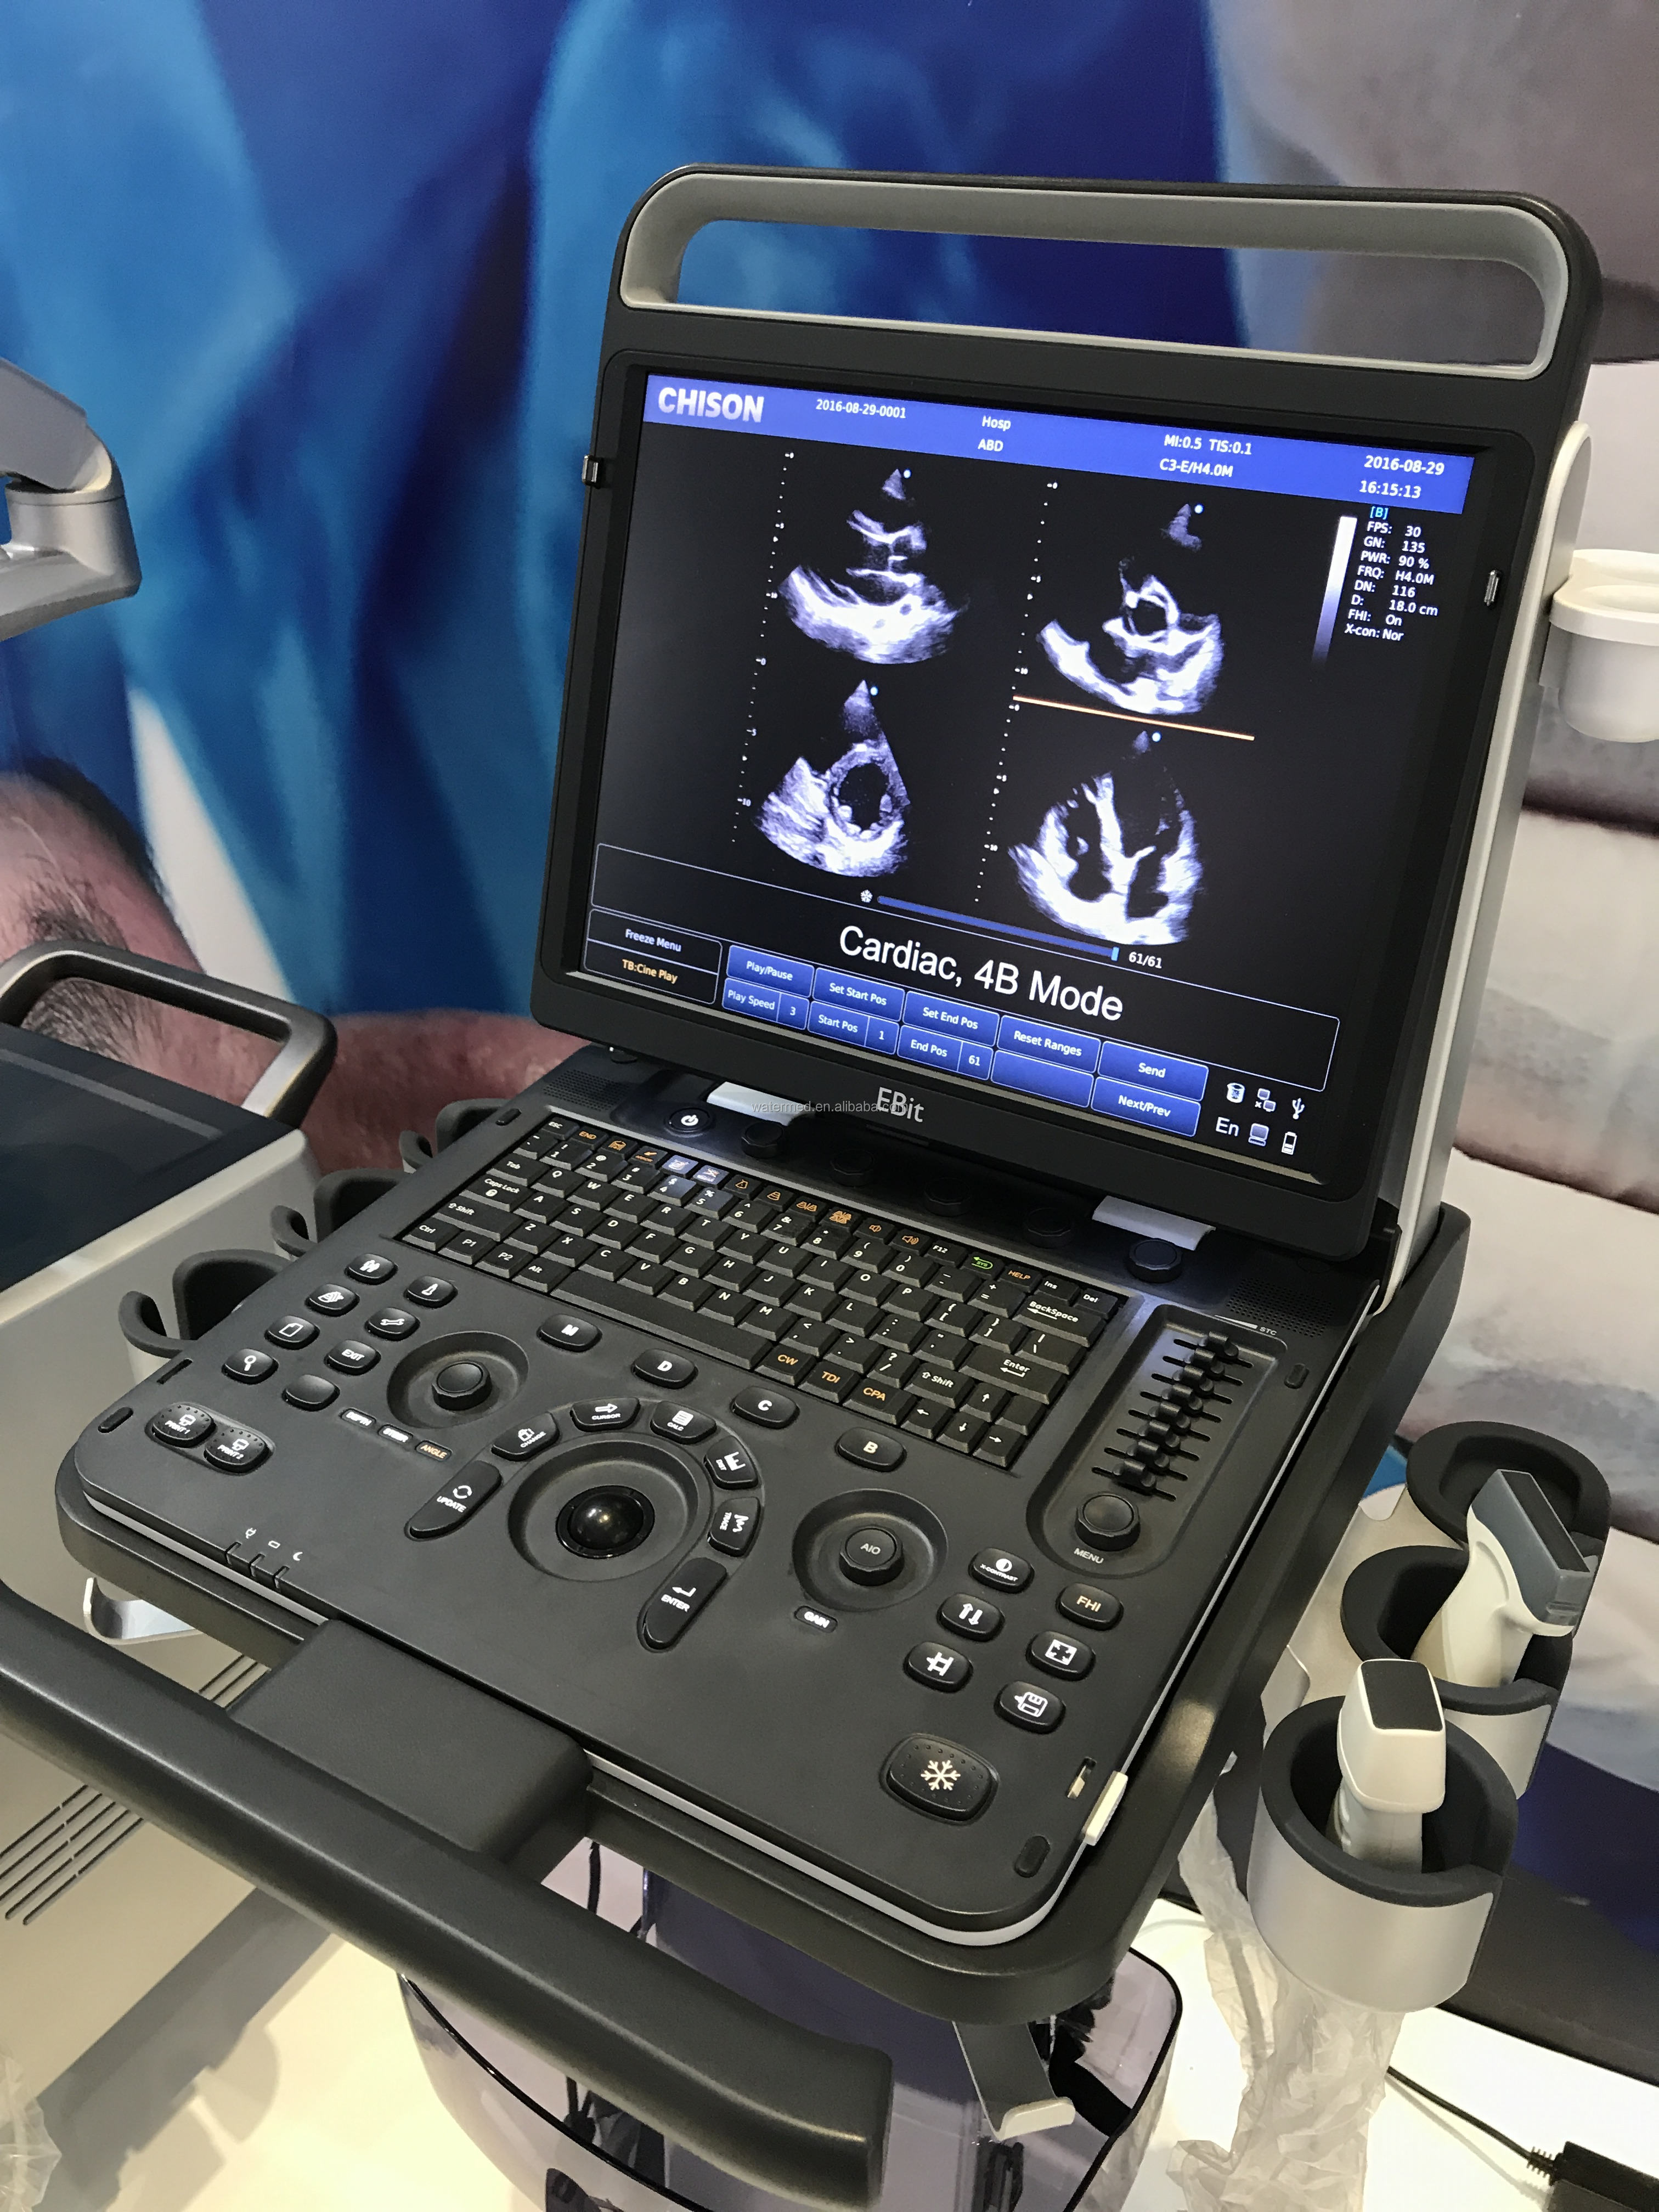

Real-time 3D (4D)

With the addition of physical channels and a new platform, the S9 delivers high-quality imaging and high frame rates to meet the new standard of the SonoScape S series. Thanks to the high frame rate and advanced technology, the S9's 4D imaging can realize the smooth movement of the fetus and provide comprehensive 4D acquisition, data rendering and post-processing functions.

With the addition of physical channels and a new platform, the S9 delivers high-quality imaging and high frame rates to meet the new standard of the SonoScape S series. Thanks to the high frame rate and advanced technology, the S9's 4D imaging can realize the smooth movement of the fetus and provide comprehensive 4D acquisition, data rendering and post-processing functions.

S9 is equipped with a high-density phased array probe to meet the needs of high frame rate and high resolution for cardiac imaging. Thanks to the high sensitivity of SonoScape color Doppler mapping, the S9 can provide an accurate cardiac diagnosis beyond your imagination.

S9 is equipped with a high-density phased array probe to meet the needs of high frame rate and high resolution for cardiac imaging. Thanks to the high sensitivity of SonoScape color Doppler mapping, the S9 can provide an accurate cardiac diagnosis beyond your imagination.